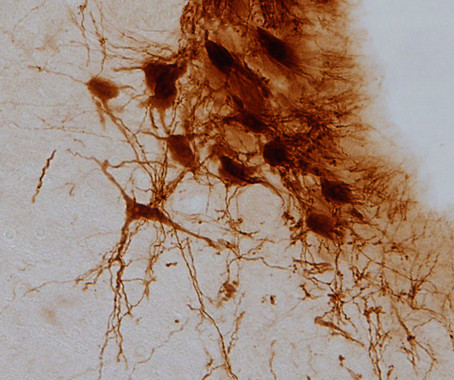

Desarrollan una aproximación farmacológica novedosa y original destinada al tratamiento de la sintomatología cognitiva de la esquizofrenia

CIBERSAM participa en el mayor estudio genético de la esquizofrenia